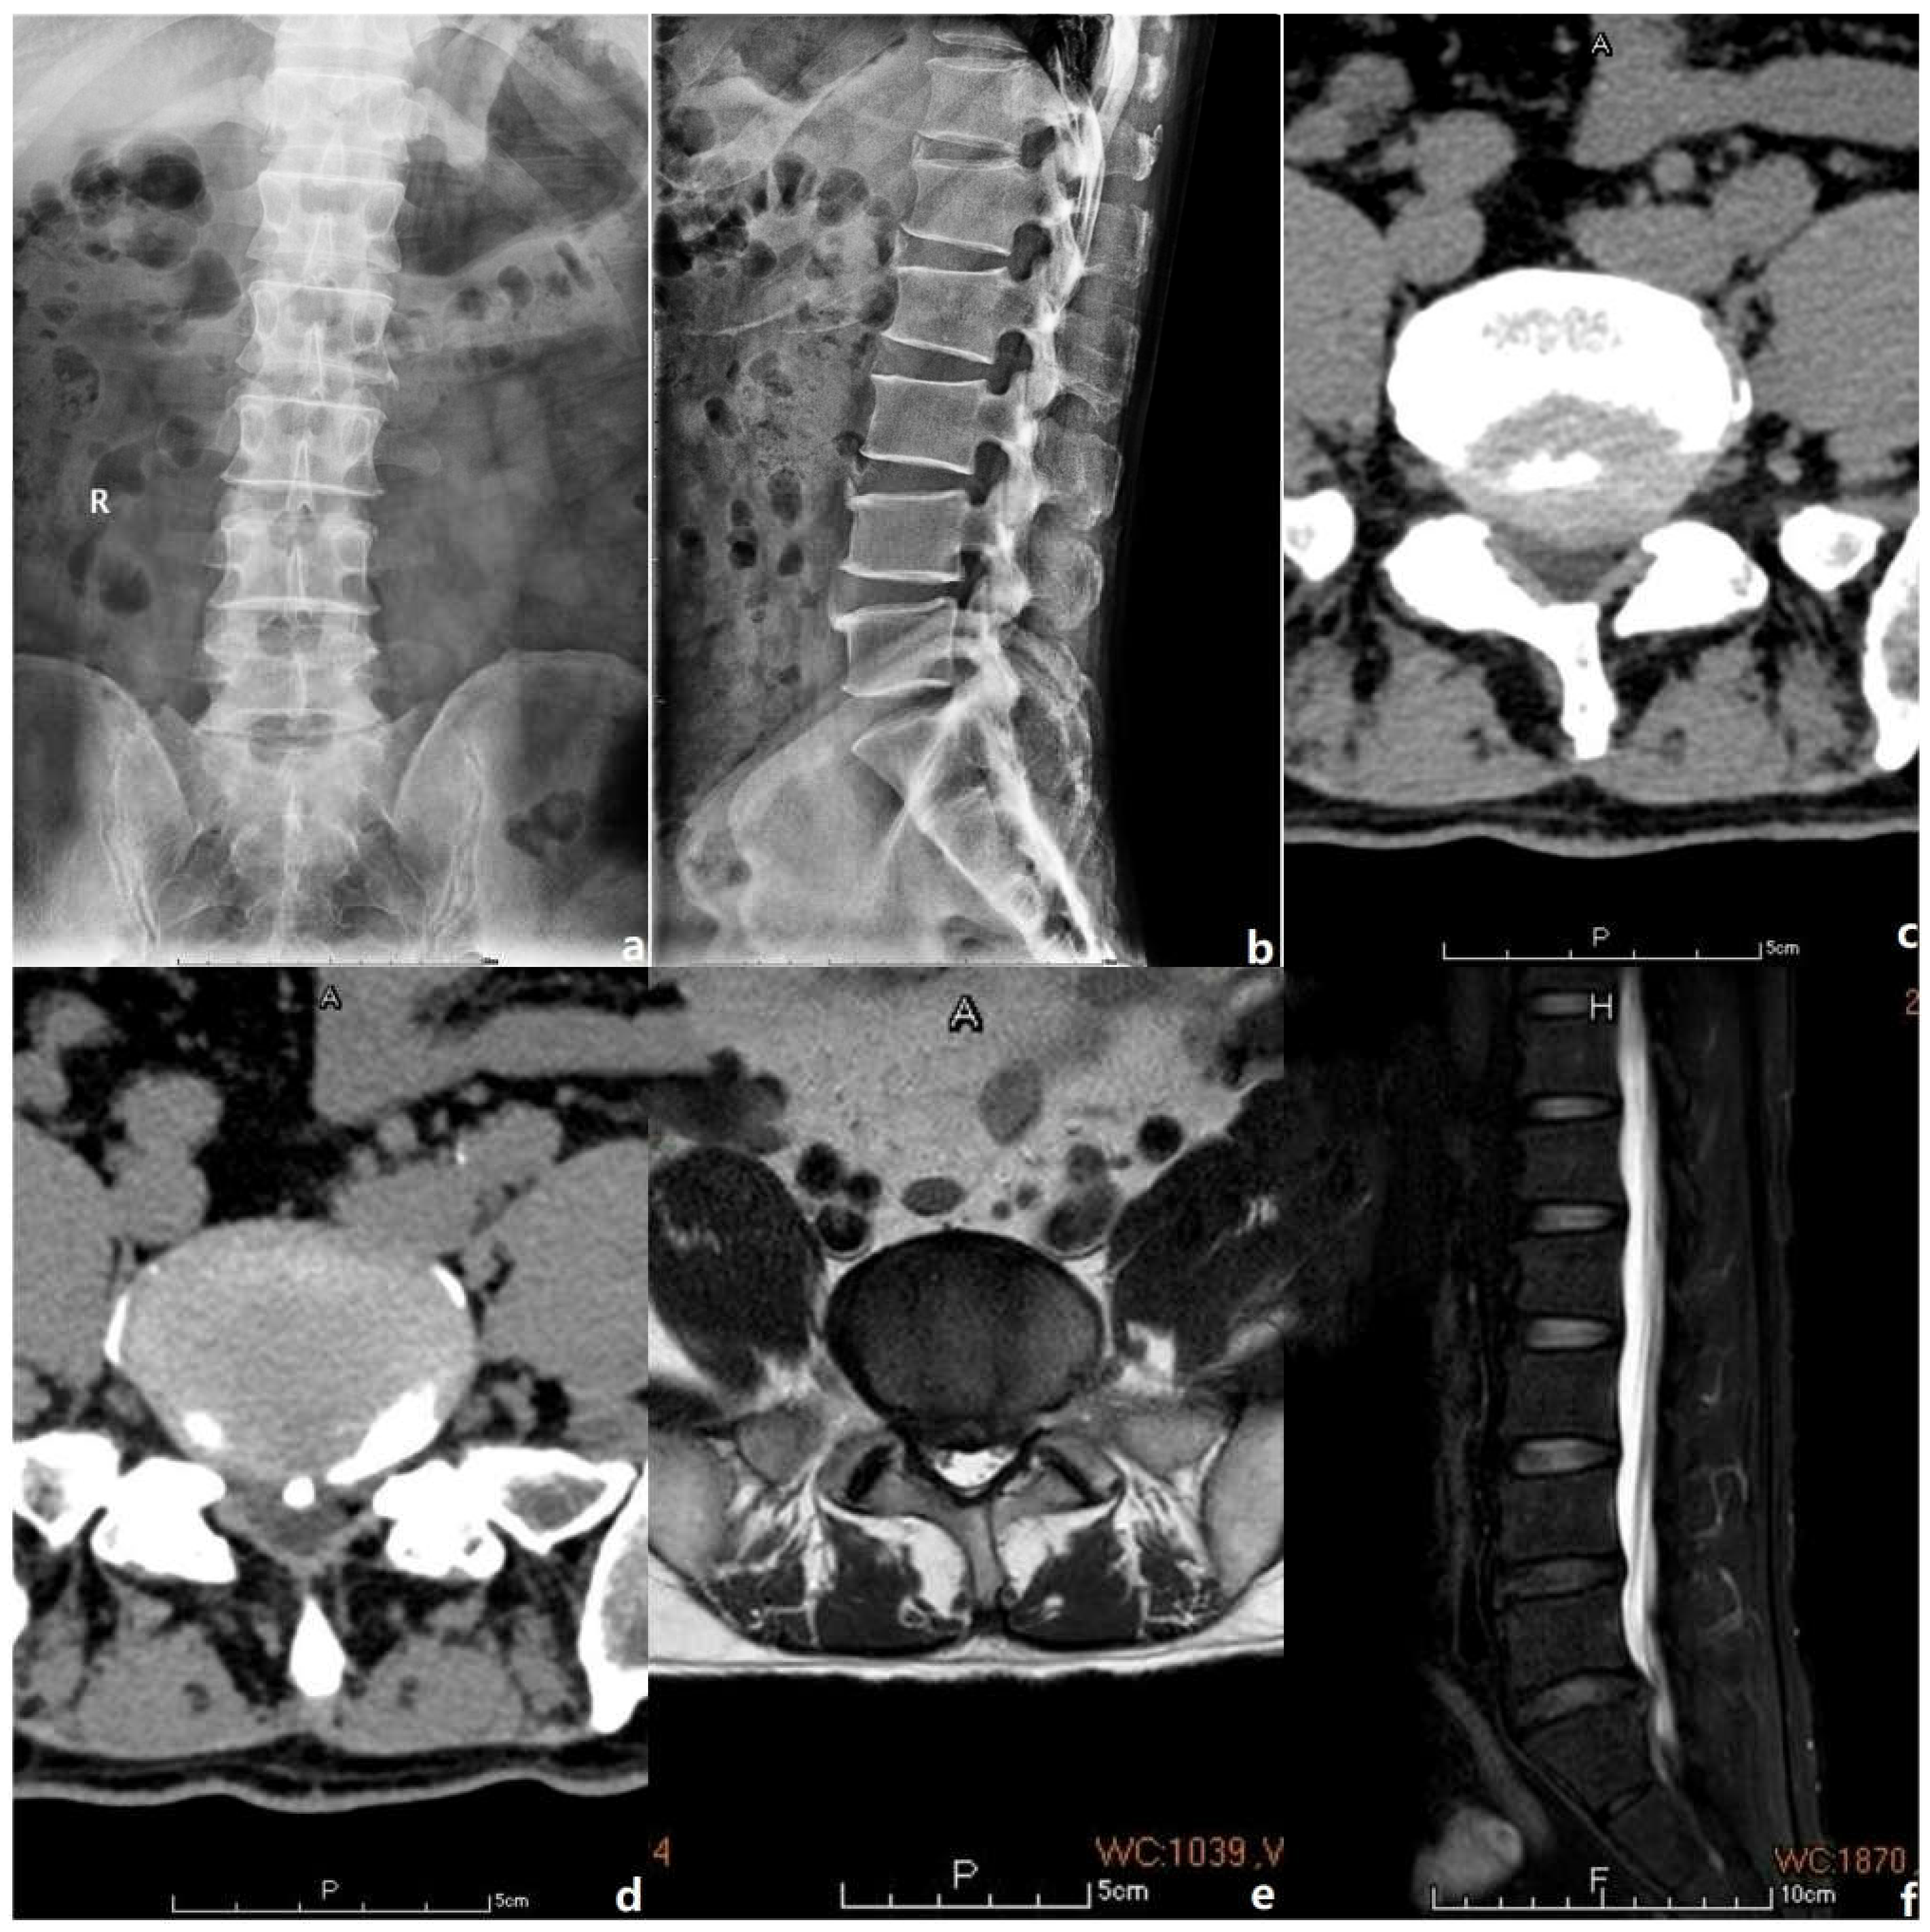

2. Case Presentation

2.2. Basic Information

2.3. Operational Procedure

2.4. Postoperative Management